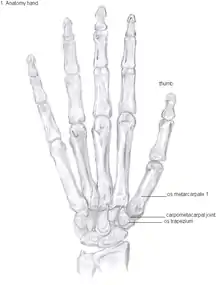

Showing the bones of the hand

The TMC joint is a synovial joint between the trapezium bone of the wrist and the metacarpal bone at the base of the thumb. This joint is a so-called saddle joint (articulatio sellaris), unlike the CMC joints of the other four fingers which are ellipsoid joints.[17] This means that the surfaces of the TMC joint are both concave and convex.